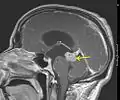

و هذه بعض التصويرات بالرنين المغناطيسي التي تكشف عن بعض الحالات الشائعة من الورم النجمي :

ورم نجمي ذو درجة منخفضة (السهم يشير إلى الورم)